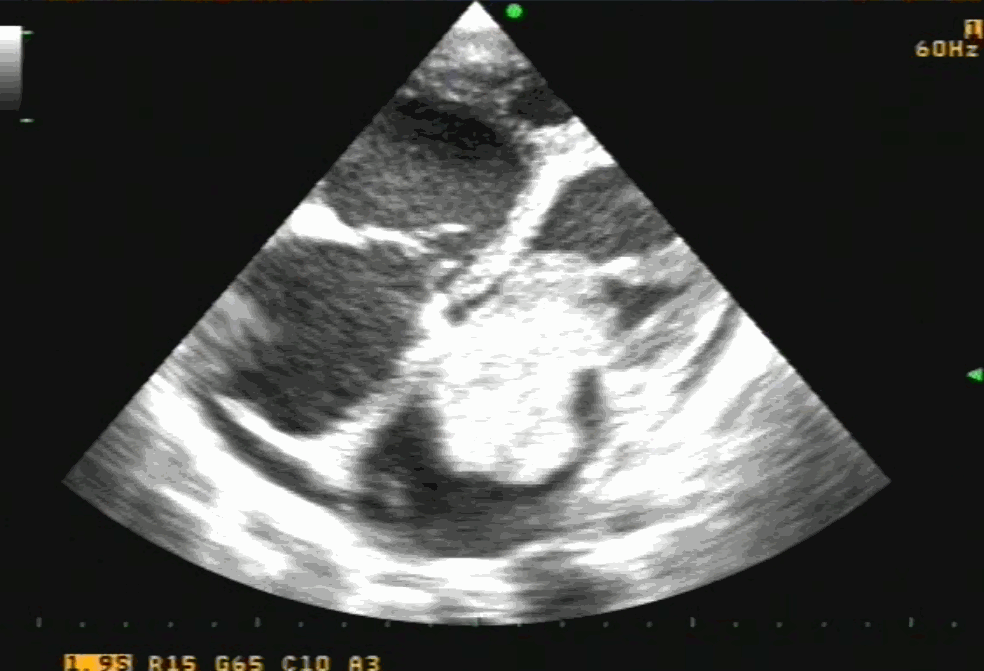

Bicaval view is an Important TEE view to visualize, the LA, IAS, and right atrium. I used to have some trouble getting oriented to this view. Hence this post. It is obtained in the 90-120 degree view at the mid esophageal position. Imagine the patient is lying on his left side and the probe comes from above down between the spine and heart to the LA from within the esophagus. This is the best view to see IAS in the profile.(Subcostal TTE can also do it) Note how the LA hugs the right atrium which is actually an ill-defined (In TEE I mean) common meeting point of both IVC and SVC. Also important is the relationship of RUPV with SVC & the horizontally running RPA sitting right over the top of LA.

The relationship between RUPV and SVC is crucial in device closure of large ASD, especially in sinus venous defect.

Clinical Importance of this view

Very useful in ASD rim morphology especially in the posterosuperior rim.

Delineates clearly the defect boundaries in SVC ASD.

This view doesn’t miss even the smallest PFO (With Contrast )

Can be used to guide IAS puncture in structural heart Interventions.

IVC /SVC mass extension into RA well visualized.